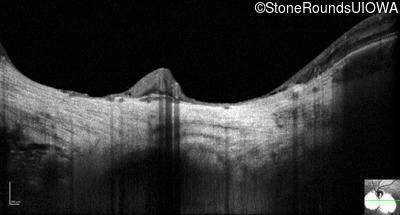

Optical Coherence Tomography - Left - 20/50 +2

Exemplar / OCT Stack

OCT Stack